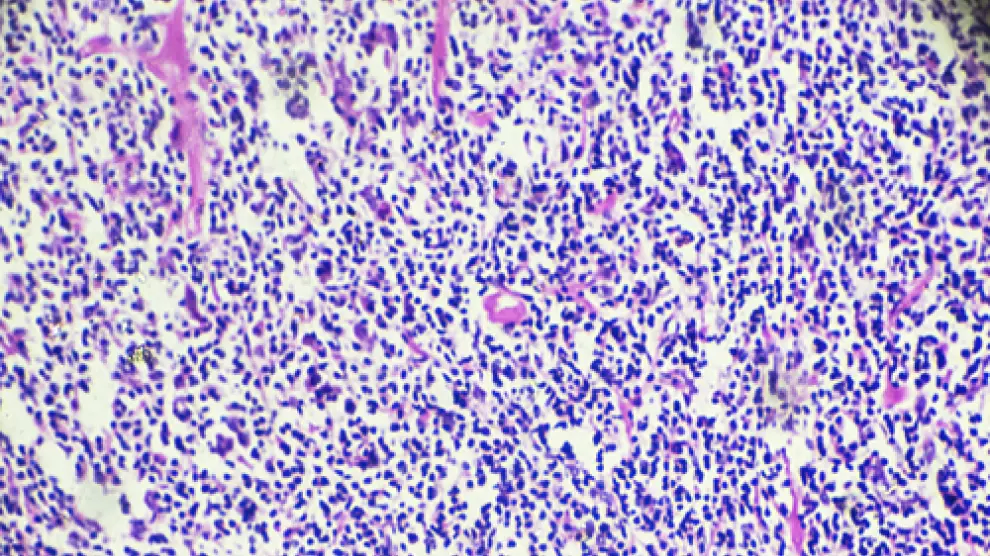

Los linfomas son cánceres que comienzan en los glóbulos blancos llamados linfocitos. Existen dos tipos principales de linfoma: Linfoma de Hodgkin (HL) y Linfoma no Hodgkin (NHL). Los dos tipos de linfoma se comportan, se propagan y responden al tratamiento de manera diferente.

Cuando las células afectadas son los linfocitos (que son un subtipo de glóbulos blancos muy importantes que forman parte de nuestras “defensas”), y se originan en el sistema linfoide (ganglios linfáticos, bazo, …), hablamos de un diagnóstico de linfoma.

El linfoma de Hodgkin se empieza a producir cuando los mecanismos de control de los linfocitos se alteran, se inicia una división celular alterada e incontrolada.